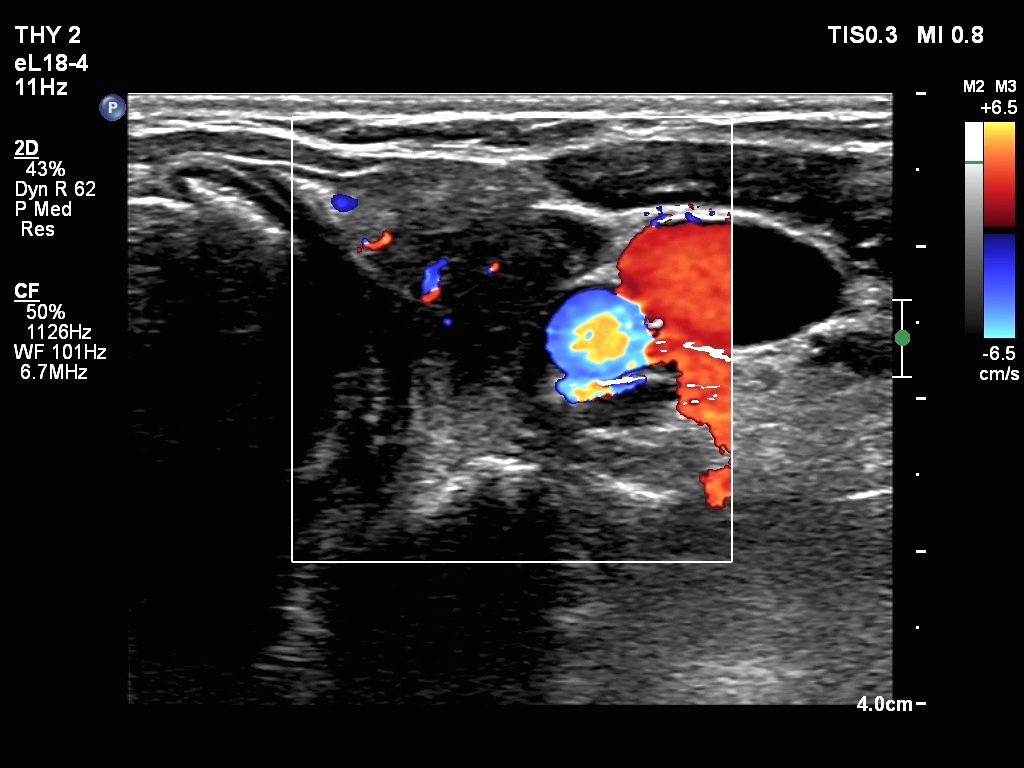

Ultrasonography. The thyroid was echonormal. There were two nodules in the right lobe. The upper was hyperechogenic-cystic while the lower was a minimally-moderately hypoechogenic. The latter had irregular, lobulated margins. There was a hypoechoic area in the upper two-third of left lobe. The discrete area presented ill-defined margins and decreased vascularization. A spongiform cyst was found in the lower pole of the left lobe.

Cytology of the nodule with irregular margins resulted in benign lesion, while cytology disclosed de Quervain's thyroiditis in the event of the hypoechoic area in the left lobe.